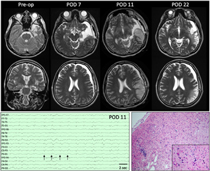

A 21-year-old right-handed female with epilepsy was admitted for presurgical work-up. Her history was significant for encephalitis 5 years earlier in China. She had focal aware seizures with auditory hallucinations and speech comprehension difficulties that occasionally evolved to bilateral tonic–clonic convulsions. Seven habitual seizures were recorded arising from the left anterior temporal lobe. Her interictal electroencephalography (EEG) showed intermittent left hemisphere slowing maximal in the anterior to mid-temporal region and occasional left anterior temporal sharp waves. Magnetic resonance imaging (MRI) demonstrated encephalomalacia in the left temporal pole, parahippocampal gyrus, and insula as well as left hippocampal atrophy (Figure 1). Interictal single photon emission computerized tomography showed left temporal hypoperfusion. Neuropsychological testing demonstrated left hemispheric language dominance and verbal memory deficits.

Figure 1: Top:Presurgical axial and coronal T2-weighted images demonstrate encephalomalacia in the left temporal pole, parahippocampal gyrus, and insula as well as volume loss in the left hippocampus. On POD 7, MRI showed a left subdural hygroma with mild mass effect and 5-mm midline shift as well as subtle signal change along the resection margin. Four days later (POD 11), MRI demonstrates left posterior temporal and parietal T2 hyperintensity that is predominantly cortical and accompanied by sulcal effacement. Additional sequences not shown demonstrate associated reduced diffusion and subtle leptomeningeal enhancement. By POD 11, overall decreased mass effect and swelling with developing extensive encephalomalacia are seen in the previously affected areas. Bottom left: EEG performed on POD 11 demonstrates lateralized periodic discharges maximum over the left hemisphere (arrows) as well as generalized slowing of background. Bottom right: Representative section of resected cortex showing features consistent with chronic sequelae of HSV encephalitis. Low-power view showing area of encephalomalcia with marked reactive astrogliosis, patchy cavitary tissue loss, mineralized neurons, and patchy mononuclear inflammation. Inset: High-power view highlighting the scattered mineralized neurons indicative of remote neuronal injury. Rare microglial nodules also identified (not shown). No evidence of active neuronophagia or other recent neuronal/tissue injury, viral inclusions or granulomatous inflammation to suggest active infection within the sampled tissue. (hematoxylin and eosin stain).

A dexamethasone taper (initial dose 4 mg Q6h) was started as a standard measure to reduce retraction swelling. On postoperative day (POD) 3, she had a habitual focal seizure with impaired verbal comprehension, head turn, and right-hand automatisms. Following this, her verbal comprehension and speech deteriorated. She was afebrile, and her white blood cell count was normal. Her anticonvulsants were adjusted. By POD 6, she suffered eight more seizures. EEG showed generalized slowing, and an MRI demonstrated subtle T2 hyperintensity adjacent to the resection (Figure 1). Maximum temperature that day was 37.6°C and white blood cell count increased to 16.1 × 109/L (4.0–11.0 × 109/L) only to fall back down to 10.2 × 109/L by POD 9. Anticonvulsants were adjusted. Her seizures were believed to have arisen from local postoperative irritation, and her dysphasia was thought to be postictal. On POD 9, she developed global dysphasia despite no obvious seizures. Continuous EEG was initiated. Three clinical and six electrographic seizures were recorded. Anticonvulsants were increased. She subsequently developed a fever of 38.4°C that increased to 40.2°C on POD 10. On POD 11, EEG showed left lateralized periodic discharges (Figure 1). A repeat MRI showed evolving T2 hyperintensity and restricted diffusion in the left posterior temporal and parietal lobes with regional leptomeningeal enhancement concerning for infectious encephalitis (Figure 1). The results of a lumbar puncture demonstrated 2.42 g/L protein (0.15–0.45 g/L), 2.6 mmol/L glucose (2.2–3.9 mmol/L), 17 × 106/L white blood cells with 67% monocytes (0–5 × 106/L), 59 × 109/L red blood cells, and xanthochromia. Empiric meningitic-dosed ceftazidime, vancomycin, ampicillin, metronidazole, and acyclovir were started. Cerebrospinal fluid (CSF) qPCR was strongly positive for HSV-1 at a cycle threshold of 24.Reference Wong, Pabbaraju, Wong and Tellier3 An autoimmune encephalitis panel including anti-N-methyl-D-aspartate was subsequently negative. Two days later, seizures had ceased and her fever abated, but she remained globally dysphasic.